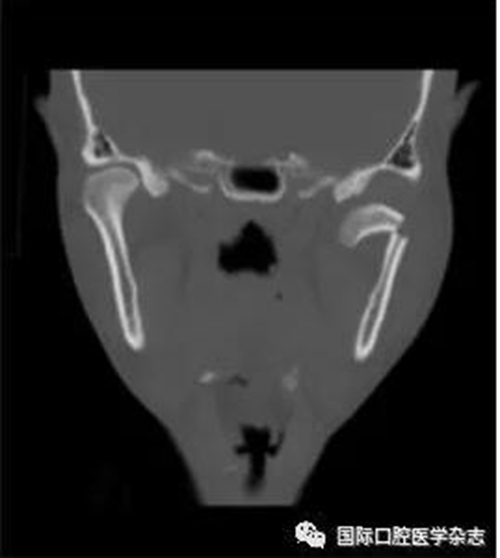

(4)關(guān)節(jié)強(qiáng)直(圖3):指因器質(zhì)性病變導(dǎo)致長期開口困難或完全不能開口??煞譃殛P(guān)節(jié)內(nèi)強(qiáng)直和關(guān)節(jié)外強(qiáng)直。關(guān)節(jié)內(nèi)強(qiáng)直是由于一側(cè)或兩側(cè)關(guān)節(jié)內(nèi)發(fā)生病變,造成關(guān)節(jié)內(nèi)的纖維性或骨性粘連,也有人稱為真性關(guān)節(jié)強(qiáng)直。關(guān)節(jié)外強(qiáng)直是病變位于關(guān)節(jié)外上下頜間皮膚、黏膜或深層肌肉組織,形成頜間瘢痕攣縮(圖4),也有人稱為假性關(guān)節(jié)強(qiáng)直[7]。5)顳下頜關(guān)節(jié)感染:常由下頜關(guān)節(jié)附近化膿性病灶所致。多見于兒童中耳炎、腮腺炎等。此外還可由全身性傳染性疾病如麻疹、猩紅熱等引起。6)顳下頜關(guān)節(jié)外傷(圖5):外傷是引起開口受限的常見因素之一,最常見于下頜骨髁突骨折引起下頜運(yùn)動(dòng)受限[8]。

圖 4 頜間攣縮